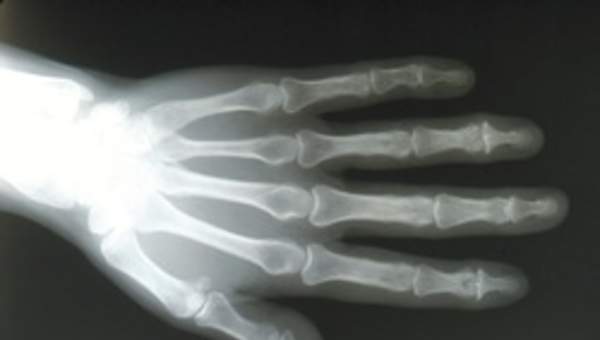

- Identifican estructuras del cuerpo humano que participan en el movimiento.

- Explican, usando un modelo simple construido por ellos, cómo participan huesos, músculos, ligamentos y tendones para permitir la flexión de una extremidad y así permitir el movimiento del cuerpo.